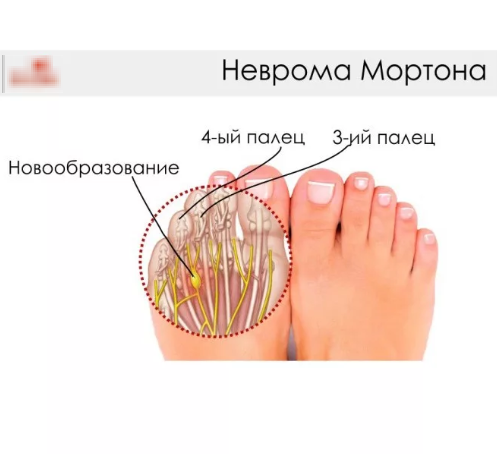

Разрастание нервной ткани, расположенной на подошве ноги, между 3-и и 4-м пальцами, называется невромой Мортона. Что это такое? Это фиброзное доброкачественное новообразование обычно поражает одну ногу, редко – обе сразу.

Как лечить неврому Мортона, придется узнать на приеме у невропатолога. Отмечается, что чаще всего неврома поражает ноги молодых женщин. Невропатолог определяет патологию в межпальцевом пространстве у третьего пальца. Здесь нарастает уплотнение тканей с сильными болями.

По анатомии на этом участке стопы нерв делится на ветви, направляющиеся к боковым поверхностям пальцев, боль расходится именно в этих направлениях. По отзывам пациентов, столкнувшихся с невромой Мортона, они уже знают, что это такое и как лечить патологию, чтобы не довести болезнь до операции.